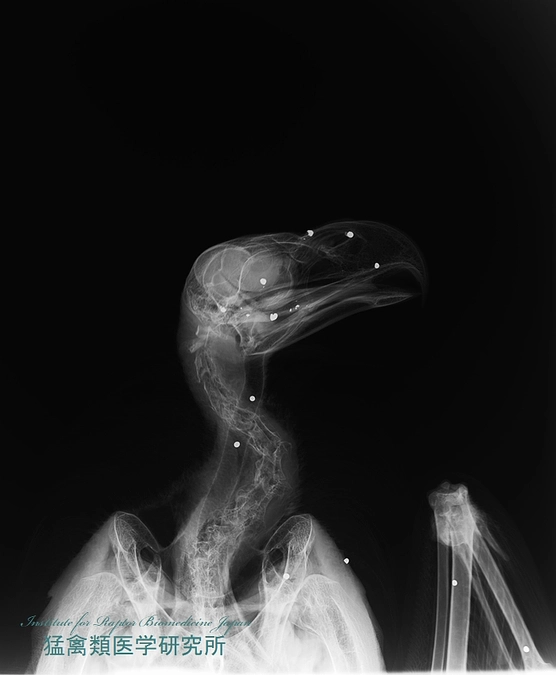

このところ毎日のように重傷の猛禽やタンチョウが運び込まれており、診察室内を含めた入院環境はほぼ満室状態です。全身麻酔下での高度な手術や点滴、酸素吸入が必要とされる動物も少なくありません。手術機器や点滴機、血液検査機器、A型インフルエンザの検査機器もフル稼働の状態で、順番待ちを余儀なくされることも少なくありません。より早く検査や治療を進めるためには、老朽化した医療機器を更新することはもちろんのこと、使用頻度が高い基礎的な医療機材を複数準備する必要性も強く感じております。また、ドクターカーの中でも現在センターでしか行えていない検査を実施しながら輸送することができれば、より早く治療に移行でき、さらに多くの命を救うことができると思われます。手術機器の数を増やすとともに、滅菌器なども充実させることにより、一日にこなせる手術の数も増やせるでしょう。連日酷使しているドクターカーや四輪駆動車のメンテナンスや不具合箇所の修理、より使いやすいものへの更新も念頭に置かなくてはならない状態になってきました。もちろん、全てを一度に実現させることはとても難しいと思っております。ただ、すぐにbestな状態にできなくても、少しでも現状よりもbetterな状態を目指し、小さな改善を積み重ねることが一羽でも多くの命を救うとともに、終生飼育個体のQOL(生活の質)を高く保ちながら継続飼育し、彼らと共に事故などの予防機材の開発などにいっそう力を入れることができると信じております。このような考えから、猛禽類医学研究所は第3目標として3500万円を設定させて戴き、皆さまと共に消えそうな命と真摯に向き合いながら“野生動物とのより良い共生社会”の実現を目指したいと思っております。引き続き、どうぞよろしくお願い申し上げます。